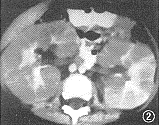

11例白血病肾浸润患儿中,9例为双肾浸润,其中双肾弥漫浸润4例,双肾多发结节浸润5例,9例中ALL 8例,ANLL 1例。CT平扫见弥漫浸润为两肾轮廓增大,肾包膜完整光滑,肾实质明显增厚,肾实质密度无异常,肾窦形态基本正常,增强后肾盂、肾盏显影轻度延迟。B超显示肾影增大、肾实质增厚的同时还显示回声均匀增强。 多发结节浸润的平扫CT见肾实质内多发的略高密度结节影,结节间可见线状低密度影将其分开(图1),结节突起使肾表面呈轻度分叶状。增强后肾实质内结节呈轻微强化,较平扫增长18 HU,密度均匀,结节内无低密度坏死区或出血,结节间见强化后受结节挤压变形的肾实质与集合系统,呈高密度分支状影(图2),肾实质强化程度较正常减低,在结节间自肾被膜下延伸至肾窦,肾盏变形拉长,肾盂显影明显延迟。B超显示肾实质回声增强,内见多发大小不等的结节(图3),中等强度回声,肾结构不清。化疗后复查,CT平扫显示双肾大小、形态基本恢复正常。本组2例呈单发结节浸润,均为ANLL。平扫CT见肾实质局限增厚,表面隆起,密度较正常肾实质略高,境界模糊(图4),增强后见肾实质内单发结节状影轻微强化,较平扫增长22HU,结节与正常肾实质间界限清楚(图5),肾被膜完整。B超显示肾实质内孤立中等强度回声结节(图6),肾结构受挤压变形。化疗后复查B超显示肾形态基本恢复正常。 本组化疗后5例复查CT与B超,显示肾轮廓明显缩小,肾实质厚度、密度或回声接近正常。11例患儿肝、脾均有不同程度增大。8例ALL患儿CT或B超检查同时显示胸腺浸润1例;肺及胸膜浸润4例;肾上腺浸润2例;腹膜后淋巴结浸润1例。3例ANLL患儿除肝、脾增大外CT或B超检查未显示其他脏器浸润。

图2 与图1同一病例。增强CT显示结节密度均匀,结节间残存肾实质呈分支状强化,肾盂显影延迟